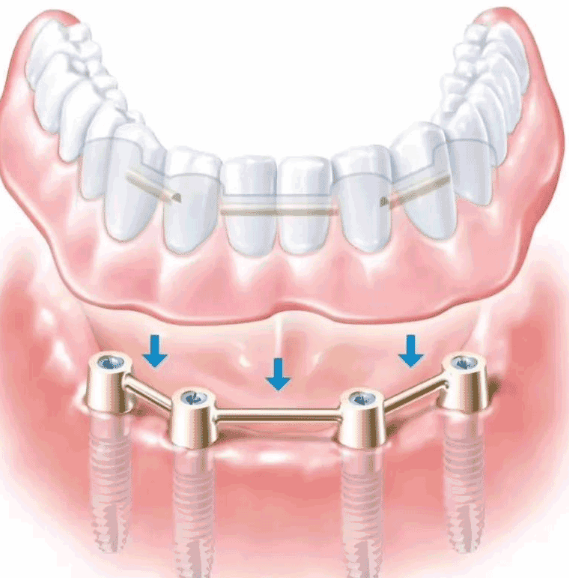

随着技术的不断成熟、完善,越来越多的人选择了种植义齿以恢复美观和功能。但是,临床上常采用的办法是拔牙后3个月先种植体植入,再经过3-6月的愈合期后,进行烤瓷牙(或全瓷牙)的修复。这个过程实际上是比较长的,所以,很多人在考虑去种牙的时候,往往也会有很多担忧。

现在,大家对多颗种植完全不必担心了。廊坊圣洁口腔引进了先进的数字化微创种植技术,它的突出特点就是即刻,能在短时间内将义齿手术完成。即刻种植缩短了治疗周期、减轻患者的痛苦等角度的考虑,越来越多合适的病例采用即刻种植修复。